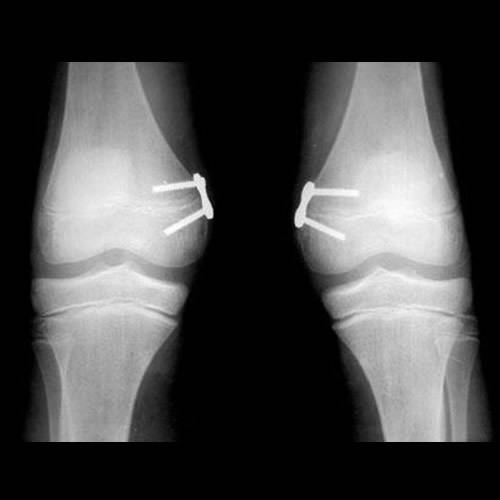

Quando há alterações estruturais sem tendência de correção natural, pode ser indicado o tratamento com cirurgia de crescimento guiado, técnica minimamente invasiva que utiliza placas metálicas para corrigir o alinhamento com o próprio crescimento da criança.